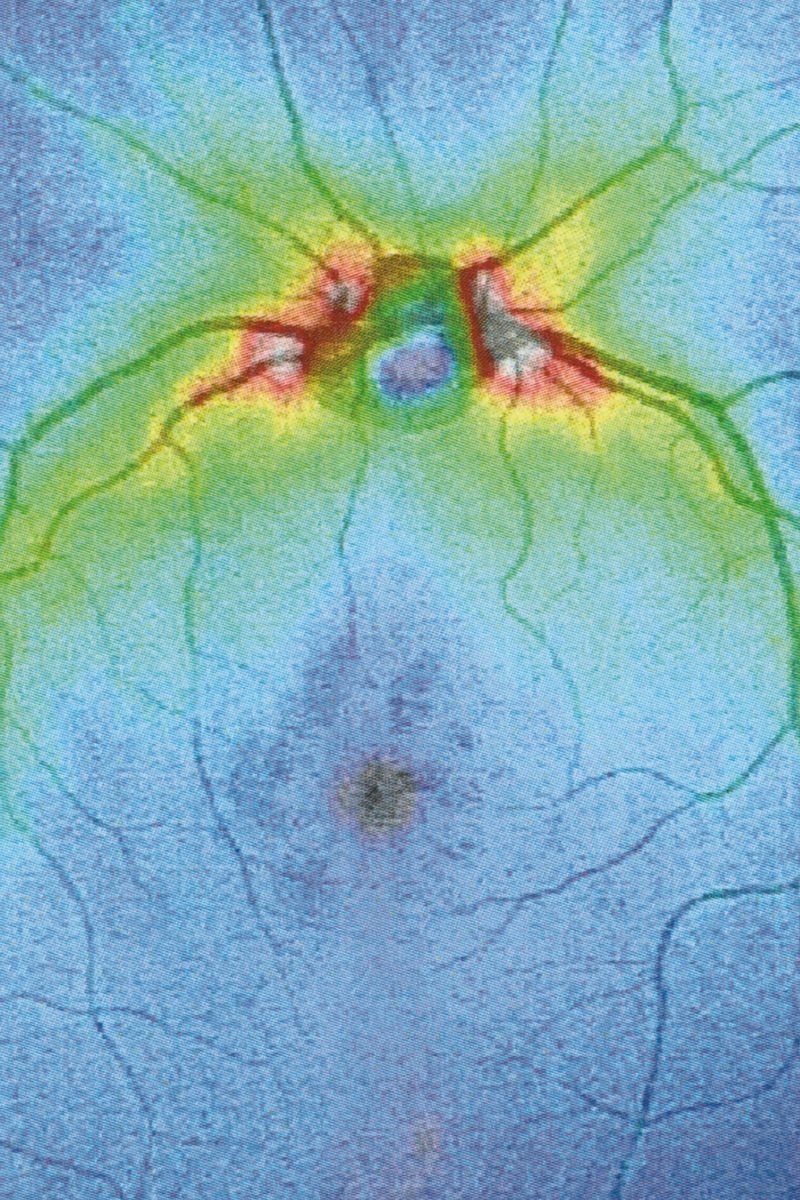

Following a terrifying experience with a too high dose of LSD when I was 16, something has changed in the way I observe visible reality. A hypertrophic screen materialized between me and the world, a scar of opacity. The fear of hallucination teaches a new language, so that every meaning remains trapped in a net and only the signifier filters through its meshes. No shadow, only empty light. Anguish arrests every retinal projection on that screen. Every perception is immobilized to be inspected for a hallucinatory return, it is reified, detached from its real referent, reduced to representation, incapable of referring to something outside of it. And behind (or in front) of it, the eyes have stolen consistency from reality. The body only appears occasionally, at the edges of the mind, when we engage in apperception. And yet I feel the tinkling of a gear that draws my attention inside my eye. I reflect on myself, I look back and from the inside. Once vision is situated in the empirical immediacy of the body, it belongs to time, to flow, to the end.

Collirio (Eye wash) is the attempt to demonstrate the non-absoluteness of visual experience, its nature as a situated, and yet, ambiguous act. It is the path that has allowed me to understand how my fears do not have roots in an unknowable place. The eye is not an unfathomable globe.